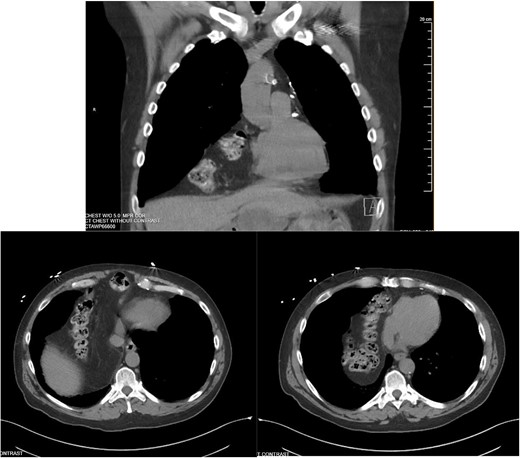

A 55-year-old male underwent lung cancer screening with a chest CT scan (Fig. 1) and was incidentally found to have an anterior diaphragmatic hernia just inferior to the sternum.

Approximately ten years prior, he had undergone coronary artery bypass surgery (CABG) with a xiphoidectomy. His symptoms at the time of the CT were right upper quadrant pain and epigastric fullness. He was referred for outpatient surgical evaluation. Shortly after the initial surgical assessment, he presented to the emergency department with gastric outlet obstruction. An abdominal CT was performed, showing a right-sided type 4 anterior diaphragmatic hernia with herniation of the antrum and pylorus causing the obstruction (Fig. 2). A loop of the transverse colon was also herniated into the thorax but without colonic obstruction.